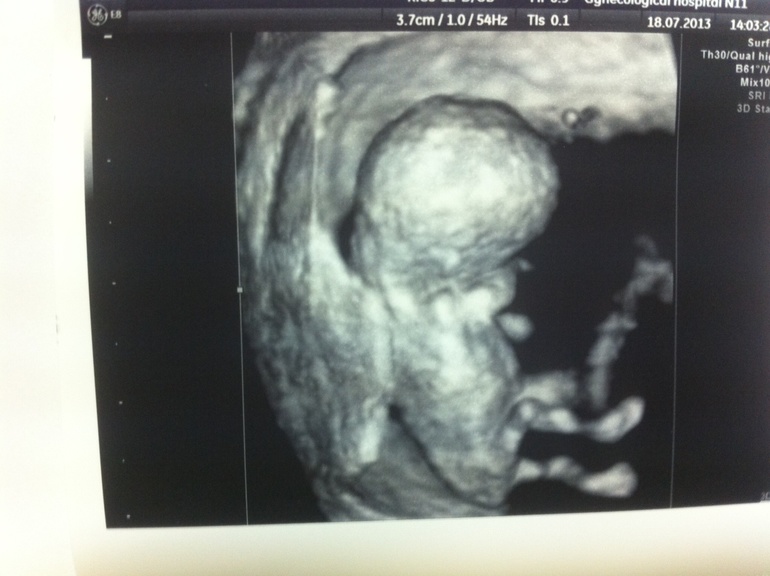

Наши 10 неделек :)

Растите здоровенькими))) даже не верится что уже такая большая котлетка)))))месяц назад просто точка а тут уже такая большая (ой) )))))вам пол не сказали еще?

Да,так быстро растет :))) половые признаки пока еще не сформированы, да это не важно :))

ЧЕЛОВЕК растет! Поздравляю, чтобы  дальше все тьфу-тьфу было!

Как мы поглядели на нашу дочурку))). Третье узи. УЗИ у Демидова (на Опарина,4)